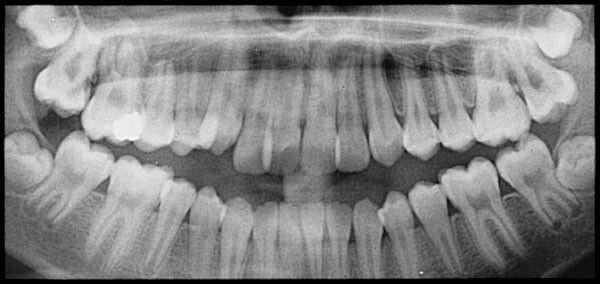

Root Resorption: What It Is And What To Do About It

Resorption occurs any time a part of the body gets absorbed into another part of the body. When we talk about tooth resorption, we generally mean the inflammation and loss of dentin (the inner tissue of the tooth) and cementum (the outer tissue of the tooth) due to absorption. Root resorption specifically refers to when the roots of a tooth or teeth get absorbed into the gums and jaw.

Root resorption is a natural part of the body’s way of recycling old tooth and bone material, and the process of the body eating away at the roots of a tooth are a natural part of losing baby teeth. But when the body starts to absorb material from the roots of permanent teeth, that’s a problem.

Root resorption in adult teeth is usually a result of some sort of trauma to the teeth, often caused by forced shifting of the teeth. This can happen after someone suffers a blow to that tooth, such as in a high-impact sport, but it can also happen as a result of orthodontic treatment.

When we wear braces, the teeth are being pushed and pulled into alignment to produce a healthier bite. Ideally, the bone should be remodeled to accommodate the new position of the teeth, but if the shift happens too quickly, the bone might not have time to readjust, leaving the roots of the teeth to decay and be absorbed back into the rest of the body. If the roots dissolve too much, they could loosen in the gums and even fall out.

In addition to the possibility that the teeth were moved too quickly in the process of orthodontic treatment, other possible factors include the duration of the orthodontic treatment, the amount of force exerted on the teeth, and the direction in which the teeth were moved.

Since no one knows for sure what causes root resorption, it’s hard to know how to prevent it, but since we know there’s a link between orthodontic treatment and root resorption, orthodontists should keep an eye on their patients’ roots. Take regular x-rays and always be on the lookout for decay.